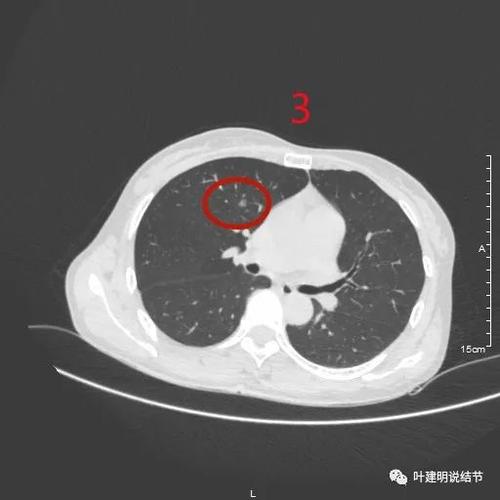

3、您好,您描述的情况考虑左肺周围型肺癌,纵隔淋巴结转移,合并心包积液的表现。肺癌患者一般会出现咳嗽、咳血、胸闷、胸痛、消瘦等等症状。中晚期肿瘤侵犯到胸膜,会出现上肢及肩部以上浮肿、静脉怒张、头痛、呼吸困难等。

4、你好,左肺癌伴肺内、纵膈淋巴结多发转移,病理类型不明,请做穿刺或气管镜活检,属于进展期的肺癌,不建议手术,立即放化疗。注:请做活检,病理结果才能确诊,才能指导下一步治疗。